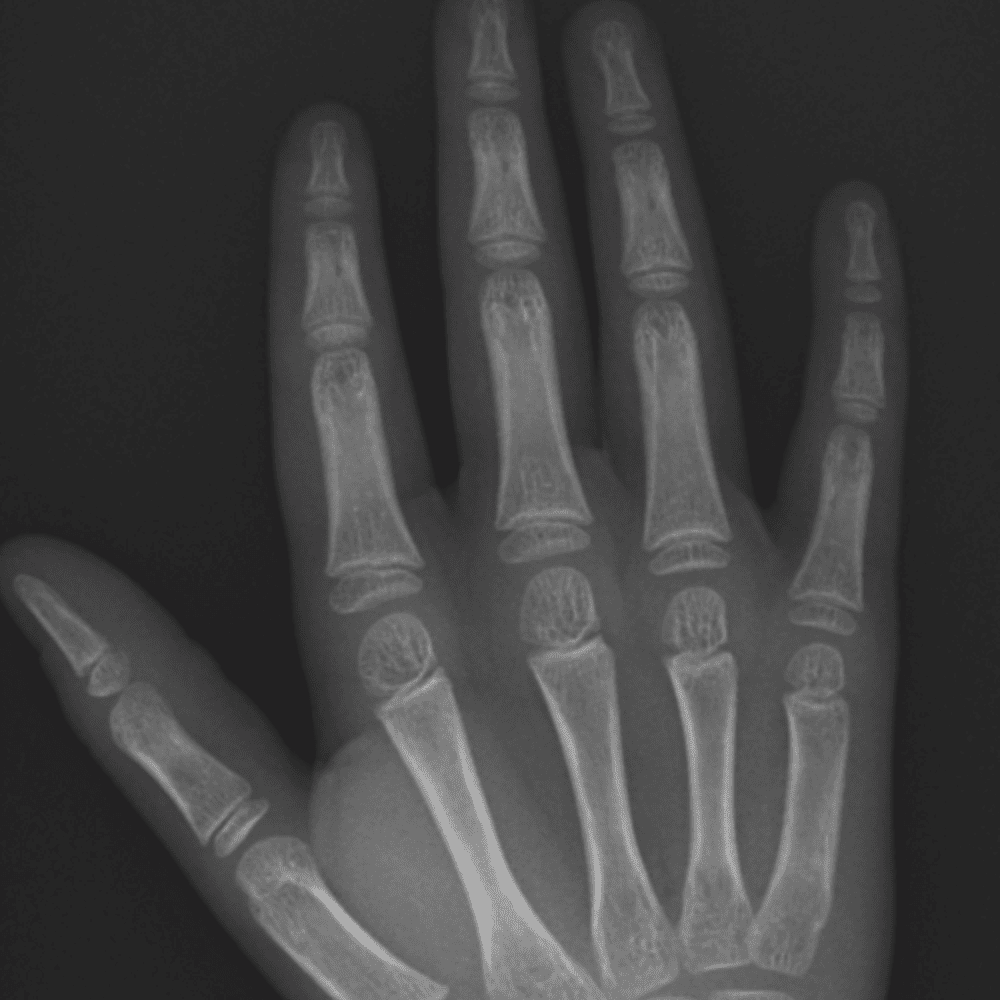

Simulates call by including subtle or difficult cases and some normals.

30 cases